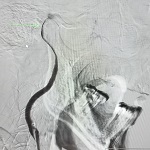

Unidad Neurovascular Innova en el tratamiento de aneurismas

con dispositivo intrasacular

Resuelven cardiopatía congénita de recién nacido por cateterismo

Procedimiento mínimamente invasivo